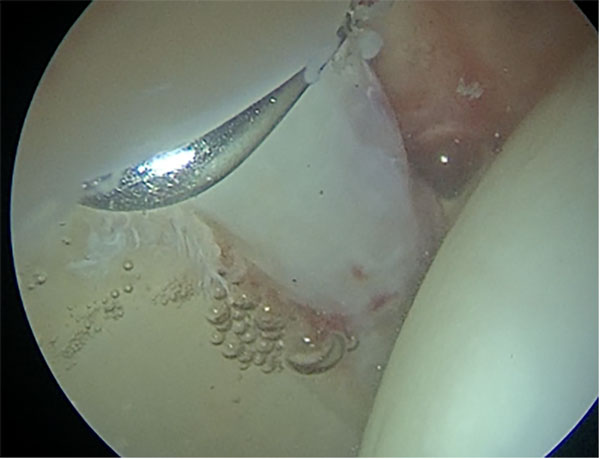

Se realizaron radiografías de anteroposterior de pelvis, perfil de cadera y de Dunn para confirmar las deformidades óseas acetabulares y femorales. Una lesión tipo Cam se define como una pérdida de la esfericidad de la cabeza femoral y un offset cabeza-cuello reducido, con un ángulo alfa mayor a 55° en la radiografía de perfil de Dunn.13 En la radiografía AP de pelvis un ángulo centro borde lateral mayor a 40° es sugestivo de una lesión de Pincer.14 Las radiografías fueron evaluadas por dos cirujanos del equipo quirúrgico tanto al inicio como al final del seguimiento. Sumado a esto se realizó: TC 3D para evaluar deformidades óseas sobre todo a nivel del techo acetabular y RM con y sin contraste de cadera para evaluar alteraciones del labrum (fig. 1) y el complejo condrolabral (con el advenimiento de la RM de 1.5/3T se deja de hacer rutinariamente RM con contraste y se opta por hacerlas sin contraste).

Figura 1: Lesión del labrum en hora 12.